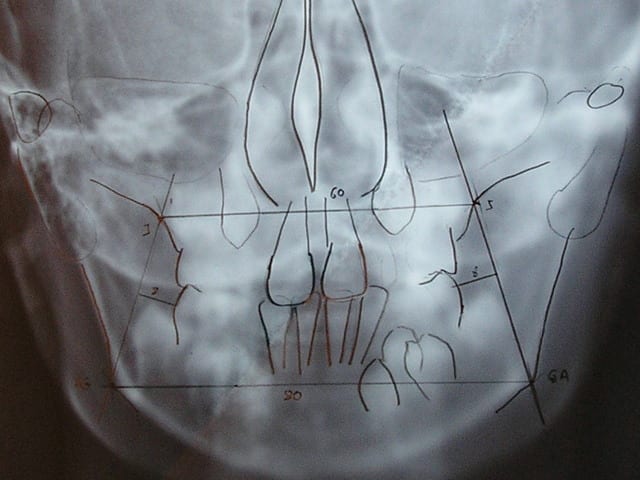

Je pense que tu vas me demander de faire une radio face pour voir le sens transversal et savoir quelles sont les possibilités de ce coté là.

la voila

Le j c téléradio face tvvhwu - Eugenol